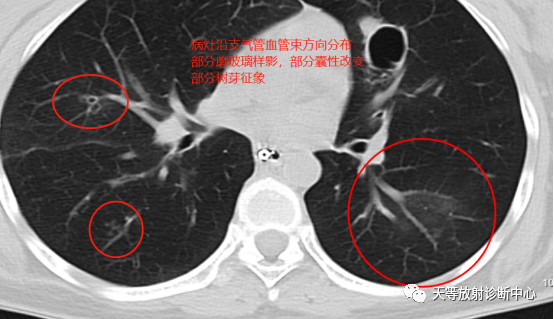

影像学表现:整体观察肺内多发病灶,散在分布,病灶的主要形态为:多发大小不等肺气囊、多发结节共同存在。

1、肺气囊大小不等,张力较大,圆形膨胀感强,周围可见大小不等结节影;

2、病灶主要沿支气管血管束方向分布,部分病灶达到胸膜下;

3、支气管间质增厚;

4、结节影大小不等,小的呈树芽征堆积,大的部分到达胸膜小,具有糊墙征,性格较温和。仔细观察病灶呈四边形、多边形,边缘刀切感,边界模糊。